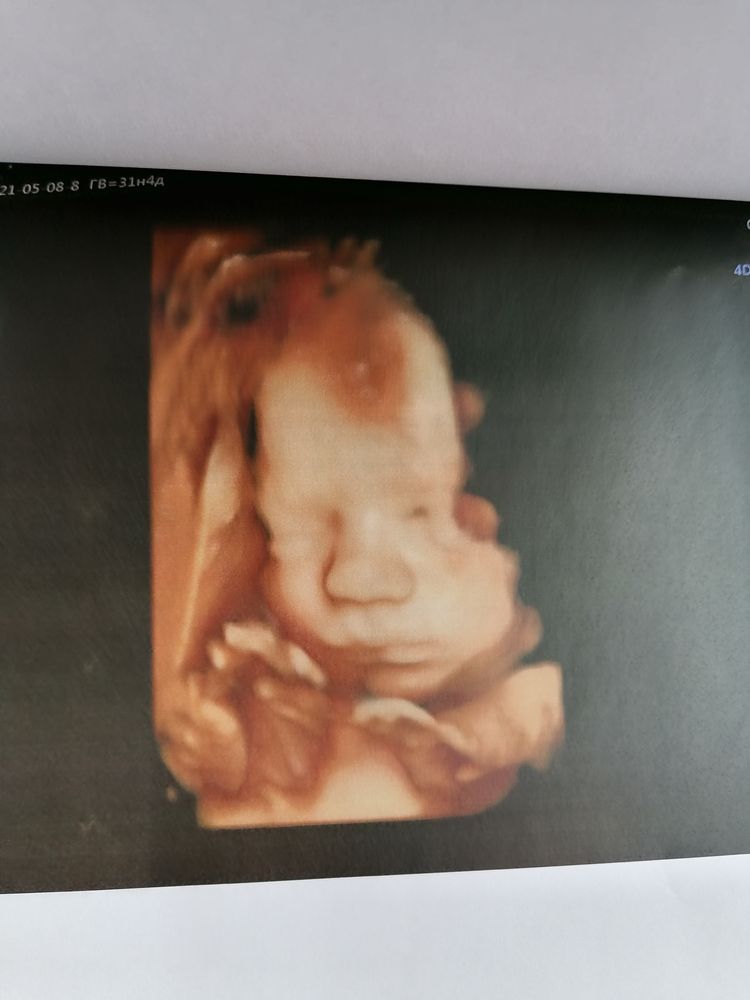

Ну а теперь о сегодняшнем скрининговом узи в 31.4 недели у Пятых Н. С.

Всё как обычно отлично, ощущение, что она нас помнит, все расспросила перед узи, пообщались. Вообщем мы с мужем довольны на все 200%. Очень тщательно рассмотрела каждый орган сыночка. Долго пытались его развернуть что бы увидеть личико и у нас получилось. Включала 4Д узи ждали пока он улыбнётся и опять таки дождались🥰.

По узи с сыночком все тттттт отлично, растёт чётко в срок, уже нет опережение. Все органы на месте, все с ними хорошо. Врач сказала, что очень большие кулачки и ножки🙈. Да я и сама видела, прям такая мужицкая рука и чувствую ух как эти кулачки и ножки🥰.

Весит 1890, что норма для 31.5 недели.

Ну и фоточки сыночка 👶🙏🙏🙏🥰. Люблю его сил нет❤️❤️❤️

Улыбашка мой